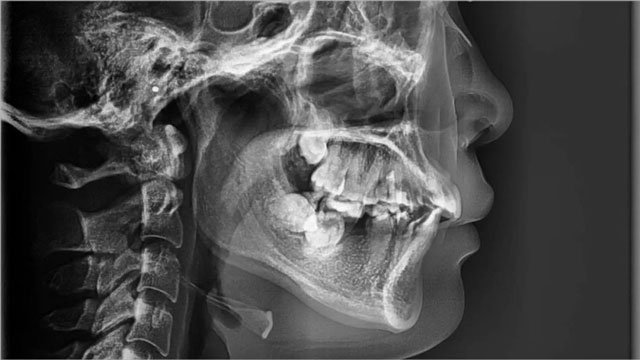

費(fèi)露:她是2021年2月來(lái)的醫(yī)院,當(dāng)時(shí)是24歲,主訴是咬合不好,檢查發(fā)現(xiàn)有3顆牙缺失,分別是一顆下前牙和下頜雙側(cè)6號(hào)牙(六齡牙);右側(cè)下頜7、8號(hào)牙向前和向舌頭一側(cè)傾斜,和上頜形成了鎖頜,這是一種不正常的咬合關(guān)系,所以她這一側(cè)基本上不能咀嚼。

她的下前牙應(yīng)該是第一次矯正時(shí)拔除的,雙側(cè)6號(hào)牙缺失是第一次矯正完成之后才出現(xiàn)的問(wèn)題,同時(shí),她下頜左側(cè)智齒為阻生牙,橫著長(zhǎng)在牙槽骨里,右側(cè)智齒只萌出了部分,整體情況比較復(fù)雜。

口內(nèi)照片及全景片(2021年2月)

側(cè)位圖(治療前)